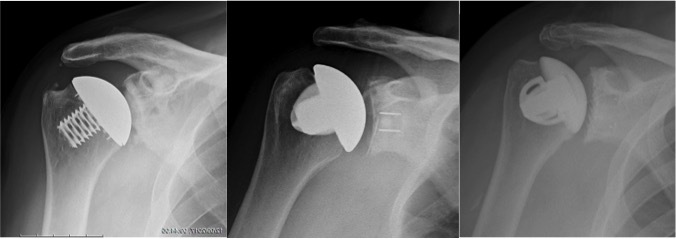

Stemless shoulder replacement: The ball of the joint is removed and replaced with a metal prosthesis fixed in the upper part of the bone but without a stem in the shaft of the humerus. The glenoid may or may not be resurfaced at the same time.

Stemmed shoulder replacement: This is the conventional type of shoulder replacement. The ball of the joint is cut and a metal prosthesis with a stem is implanted in the humerus. If only the ball of the joint is replaced the procedure is called a Hemiarthroplasty. If the glenoid is replaced at the same time the procedure is referred to as a Total shoulder replacement.